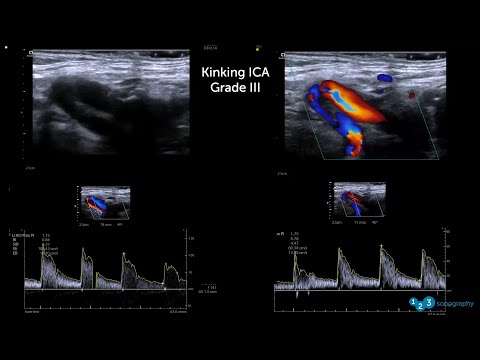

HomeResourcesVascularArterialCarotid artery Carotid artery Filter Showing all 9 results Default Sorting Sort by popularity Sort by latest Sort by editor review Dissection (1) Added to wishlistRemoved from wishlist 0 Carotid Artery Color/Spectral Doppler Ultrasound Normal Vs Abnormal Images | ICA Stenosis USG View + Added to wishlistRemoved from wishlist 0 Carotid Artery Doppler Ultrasound Reporting | How To Write USG Report | Stenosis USG Scan Reports View + Added to wishlistRemoved from wishlist 0 Carotid Dissection: Butterfly iQ Clinical Image View + Added to wishlistRemoved from wishlist 0 How to scan the carotid arteries View + Added to wishlistRemoved from wishlist 0 How to scan the carotid arteries View + Added to wishlistRemoved from wishlist 0 How To: Carotid Intima Media Thickness Ultrasound (CIMT) Exam – Scanning Techniques Video View + Added to wishlistRemoved from wishlist 0 Spring Ultrasound Knowledge Booster #7: Twists and Turns in Carotid Ultrasound View + Added to wishlistRemoved from wishlist 0 Spring Ultrasound Knowledge Booster #7: Twists and Turns in Carotid Ultrasound View + Added to wishlistRemoved from wishlist 0 Ultrasound Education: Pulsed Wave Doppler mode on the Vascular: Carotid Preset View +